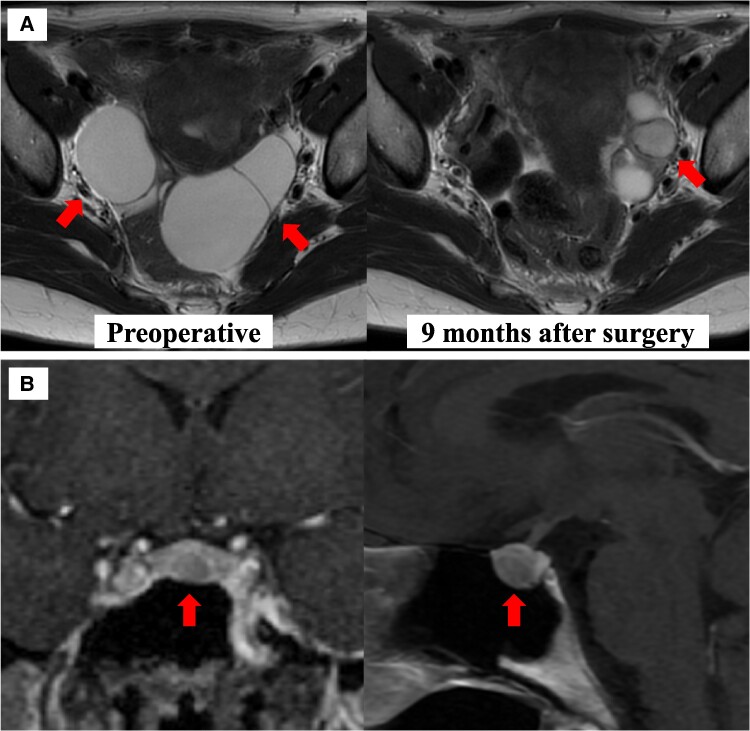

A 49-year-old woman presented with irregular menstrual bleeding, elevated estradiol (E2) (665 pg/mL [2441.21 pmol/L]) (reference range [RR]: menstrual period [MP] 20-50 pg/mL; 73.42-183.55 pmol/L), unsuppressed follicle-stimulating hormone (FSH) (19.3 mIU/mL [19.3 IU/L]) (RR: MP 3.5-10.0 mIU/mL; 3.5-10.0 IU/L), and cystic ovarian enlargement (right ovary, 109 mL; left ovary, 146 mL). A 7-mm pituitary microadenoma was also observed, and 6 months after referral, endoscopic transsphenoidal surgery was performed, resulting in a diagnosis of FSH-producing pituitary adenoma. Nine months postoperatively, the ovarian cysts had markedly shrunk. Although FSH-producing pituitary adenomas are rare, approximately 64% of nonfunctioning pituitary adenomas are positive for gonadotropin immunostaining. FSH-producing pituitary adenomas are often endocrinologically silent, with symptoms typically triggered by pituitary tumor enlargement. Early diagnosis can be facilitated by measuring FSH and E2 levels in cases of irregular vaginal bleeding, abnormal menstruation, ovarian enlargement, ovarian hyperstimulation syndrome, or infertility. If E2 is elevated but FSH is not suppressed, pituitary magnetic resonance imaging should be performed to identify FSH-producing pituitary adenomas. In cases of FSH-producing pituitary adenomas, including microadenomas, symptoms may improve after tumor resection, making surgery the preferred treatment option.